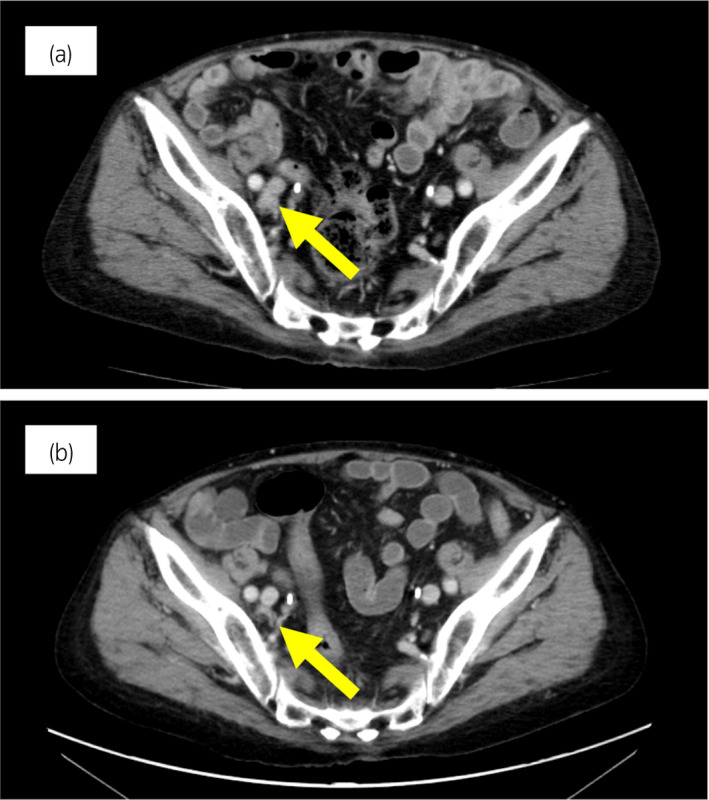

一名 78 歲男性被診斷為 cT3bN0M0,GS 為 4 + 4 =⟩8,PSA 水平為 15.2 ng/ml 7 年前,并接受了前列腺切除術(shù)。 六個月后,PSA 升高并開始雄激素剝奪治療。 兩年后,開始使用比卡魯胺治療 CRPC。 服用比卡魯胺五個月后,患者被轉(zhuǎn)診至佳學(xué)基因檢測合作醫(yī)院。 在接下來的 2 年內(nèi),依次給予恩雜魯胺、多西他賽和卡巴他賽。 多西他賽前的 MRI 顯示髂骨轉(zhuǎn)移,多西他賽和卡巴他賽治療后消失。 開始使用卡巴他賽后 6 個月,他出現(xiàn)雙側(cè)盆腔淋巴結(jié)腫大,并在膀胱后壁發(fā)現(xiàn)轉(zhuǎn)移性腫瘤。 在進(jìn)行經(jīng)尿道切除術(shù) (TUR) 期間,從膀胱中的轉(zhuǎn)移性腫瘤獲得組織樣本。 病理檢查顯示嗜鉻粒蛋白 A 陽性,NSE 水平升高,因此我們診斷為 NEPC。 卡鉑和依托泊苷聯(lián)合治療縮小了腫瘤。 此后,在 24 個月內(nèi)進(jìn)行了 17 個療程,疾病得到控制。 由于神經(jīng)病變和疲勞而停止化療。 隨后,患者出現(xiàn)盆腔淋巴結(jié)轉(zhuǎn)移進(jìn)展(圖 4a)。 通過血液檢測 (BRCAnalysis®?) 進(jìn)行的基因檢測對 BRCA 突變呈陰性。 使用 TUR 時收集的膀胱轉(zhuǎn)移組織進(jìn)行腫瘤正確用藥850基因檢測。 結(jié)果顯示,該患者的體細(xì)胞 BRCA2 突變呈陽性。 在奧拉帕尼給藥后的 3 個月內(nèi),淋巴結(jié)從 21.0mm 縮小到 7.5mm(圖 4b)。 PSA 從 1.42 下降到 0.07 ng/ml,NSE 從 22.3 下降到 11.8 ng/ml。

圖 4:病例 2:奧拉帕尼治療前和治療后 3 個月的盆腔淋巴結(jié) CT 圖像。 (a) 治療前和 (b) 奧拉帕尼治療后 3 個月。 黃色箭頭顯示轉(zhuǎn)移淋巴結(jié)。